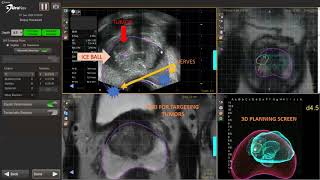

Focal Prostate Cancer Cryoablation using MR US fusion guidance (UroNav) video

Focal Prostate Cancer Cryoablation using MR US fusion guidance (UroNav)

Focal Prostate Cancer Cryoablation using MR US fusion guidance (UroNav) MRI-Guided Focal Therapy of the Prostate Using Cryoablation

MRI-Guided Focal Therapy of the Prostate Using Cryoablation MRUS Fusion Target Office Cryoablation

MRUS Fusion Target Office Cryoablation Focal Cryoablation for Prostate Cancer using MRI-Ultrasound fusion technique